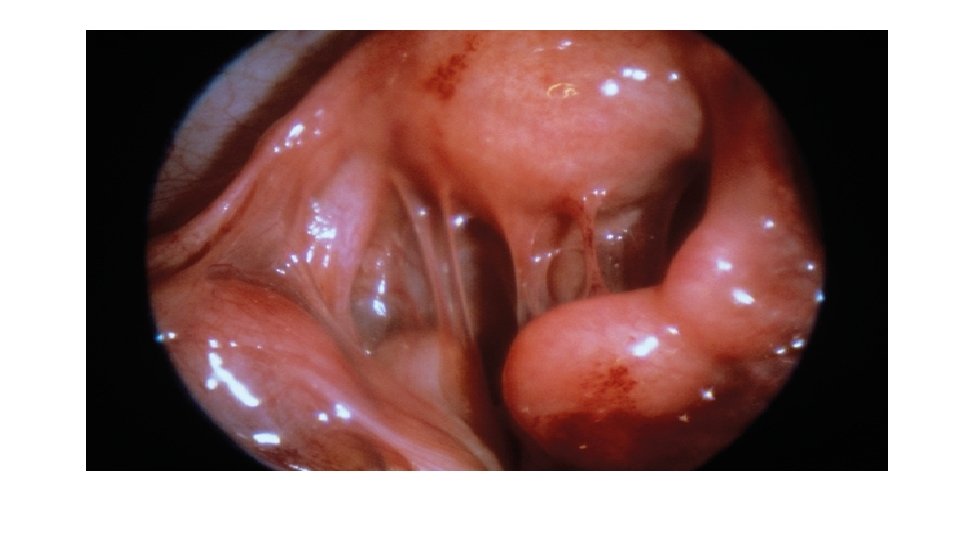

Chronic PID Investigations: . Pelvic ultrasound fixed RVF uterus, cystic pelvic mass . HSG tubal obstruction, hydrosalpinx . D laparoscopy pelvic adhesions (frozen pelvis) pelvic mass

Chronic PID - Chronic inflammation may result in occlusion of one or both ends of the tube, accumulation of fluid within the tubal lumen, tubal distension serous fluid hydrosalpinx purulent fluid pyosalpinx - Healing of the inflamed pelvic structures will result in adhesion formation mainly posterior to the uterus. These adhesions may be: mild severe

Chronic PID Clinical picture: O/E: . Patient looks toxic. Lower abdominal & pelvic tenderness. Fixed RVF uterus. Cystic pelvic mass (hydrosalpinx, pyosalpinx, tubo-ovarian abscess)